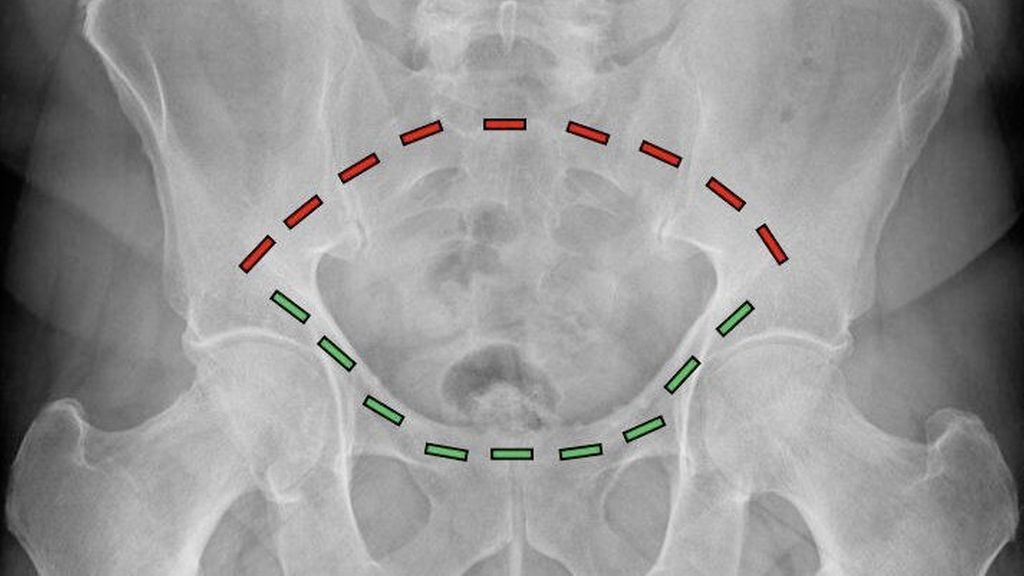

Abb. 1: Der Beckenring besteht aus einem vorderen (grüne Striche) und einem hinteren (rote Striche) Anteil. Während der vordere Beckenring durch die Schambeine gebildet wird, besteht der hintere Beckenring aus dem Kreuzbein und den Darmbeinen

FFP-Frakturen des geriatrischen Patienten entstehen im Gegensatz zu Beckenfrakturen des adulten Patienten als Folge eines niedrigenergetischen Traumas. Aufgrund der reduzierten Knochenqualität reichen also geringe Energiemengen aus, um das osteoporotisch veränderte Becken zu brechen. Für das Verständnis der Architektur des Beckens ist es entscheidend zu wissen, dass das Becken aus einer zusammengesetzten Ringkonstruktion besteht, wobei ein vorderer und ein hinterer Beckenring unterschieden werden (Abb. 1). Aufgrund des Kraftflusses, der aus dem Bein hauptsächlich über den hinteren Beckenring in den Rumpf verteilt wird, ist der hintere Beckenring für die Gesamtstabilität des knöchernen Beckens von primärer Bedeutung. Die FFP-Klassifikation gibt hier anhand der Beteiligung der unterschiedlichen Anteile des Beckenringes den gegenwärtig vollständigsten Überblick.1 In Abhängigkeit davon, ob es sich um ein- oder beidseitige Verletzungen des vorderen, des hinteren oder beider Beckenringe handelt, unterteilt diese Klassifikation in aufsteigendem Schweregrad die Verletzungsausprägung. Der Fokus der Behandlung der FFP-Frakturen liegt ebenso wie auch bei der Behandlung der Beckenverletzungen des Erwachsenen auf der Stabilisierung des hinteren Beckenringes. Im Gegensatz zu den Beckenringfrakturen des Erwachsenen, deren Entstehung eine hohe Verletzungsenergie und damit verbundene, lebensbedrohliche Begleitverletzungen wie Blutungen beinhalten, stehen bei den FFP-Frakturen aufgrund der niedrigen Verletzungsenergie die Schmerzbehandlung und die zügige Mobilisierung des Patienten im Vordergrund. Als ursächliche Mechanismen der Entstehung einer FFP-Verletzung gelten Stürze im häuslichen Umfeld bei geringer Fallhöhe und niedriger Aufprallenergie.